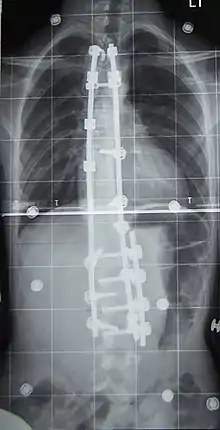

Surgery

Surgery is usually recommended by orthopedists for curves with a high likelihood of progression (i.e., greater than 45–50° of magnitude), curves that would be cosmetically unacceptable as an adult, curves in people with spina bifida and cerebral palsy that interfere with sitting and care, and curves that affect physiological functions such as breathing.[101][102]

Surgery is indicated by the Society on Scoliosis Orthopaedic and Rehabilitation Treatment (SOSORT) at 45–50°[4] and by the Scoliosis Research Society (SRS) at a Cobb angle of 45°.[103] SOSORT uses the 45–50° threshold as a result of the well-documented, plus or minus 5° measurement error that can occur while measuring Cobb angles.[103]

Surgeons who are specialized in spine surgery perform surgery for scoliosis. To completely straighten a scoliotic spine is usually impossible, but for the most part, significant corrections are achieved.[104]

The two main types of surgery are:[105]

- Anterior fusion: This surgical approach is through an incision at the side of the chest wall.

- Posterior fusion: This surgical approach is through an incision on the back and involves the use of metal instrumentation to correct the curve.

One or both of these surgical procedures may be needed. The surgery may be done in one or two stages and, on average, takes four to eight hours.